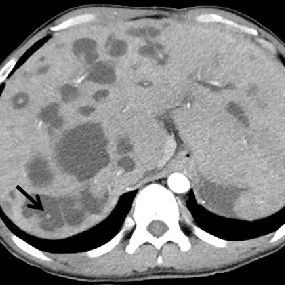

肝脓肿影像诊断

*仅供医学专业人士阅读参考肝脓肿影像表现本文首发:徐医附院影像科责任编辑:孙颖版权申明 本文转载 欢迎转发朋友圈- End -*医学界力求其发表内容在审核通过时的准确可靠,但并不对已发表内容的适时性,以及所引用资料(如有)的准确性和完整性等作出任何承诺和保证,亦不承担因该些内容已过时、所引用资料可能的不准确或不完整等情况引起的任何责任。请相关各方在采用或者以此作为决策依据时另行核查。...